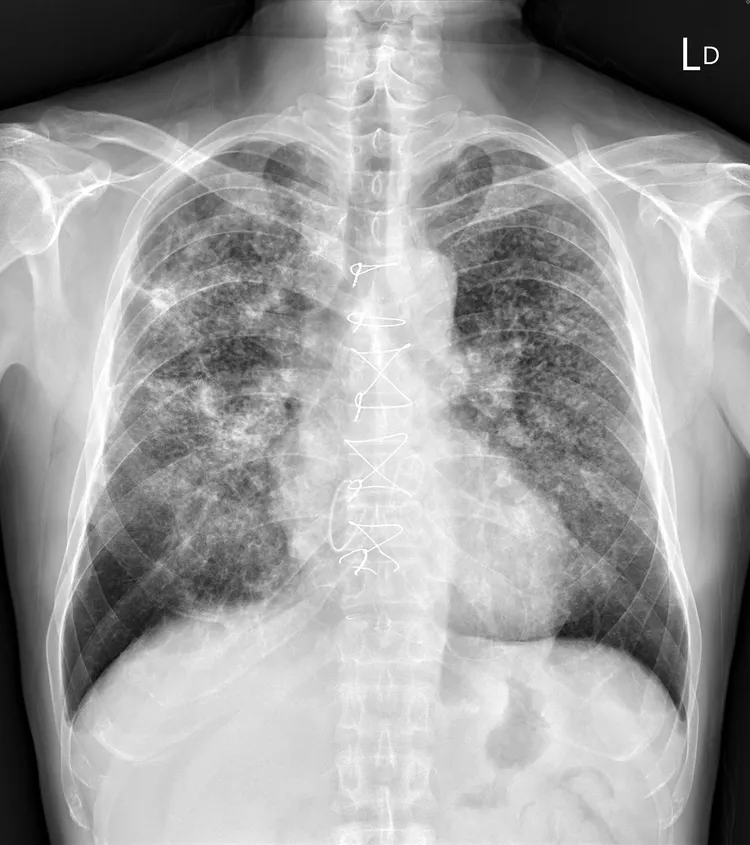

蘇一峰在臉書發文表示,一名40歲男患者不抽菸,但喘了幾個月因此到胸腔科治療,結果發現他十隻手指幾乎都是杵狀指,因此也安排他照X光,「X光就看到滿天星的肺結節,成千上萬顆肺結節,讓密集恐懼症的人頭皮發麻」。

40歲男X光照出成千上萬顆肺結節。翻攝蘇一峰臉書

40歲男胸部X光。翻攝蘇一峰臉書